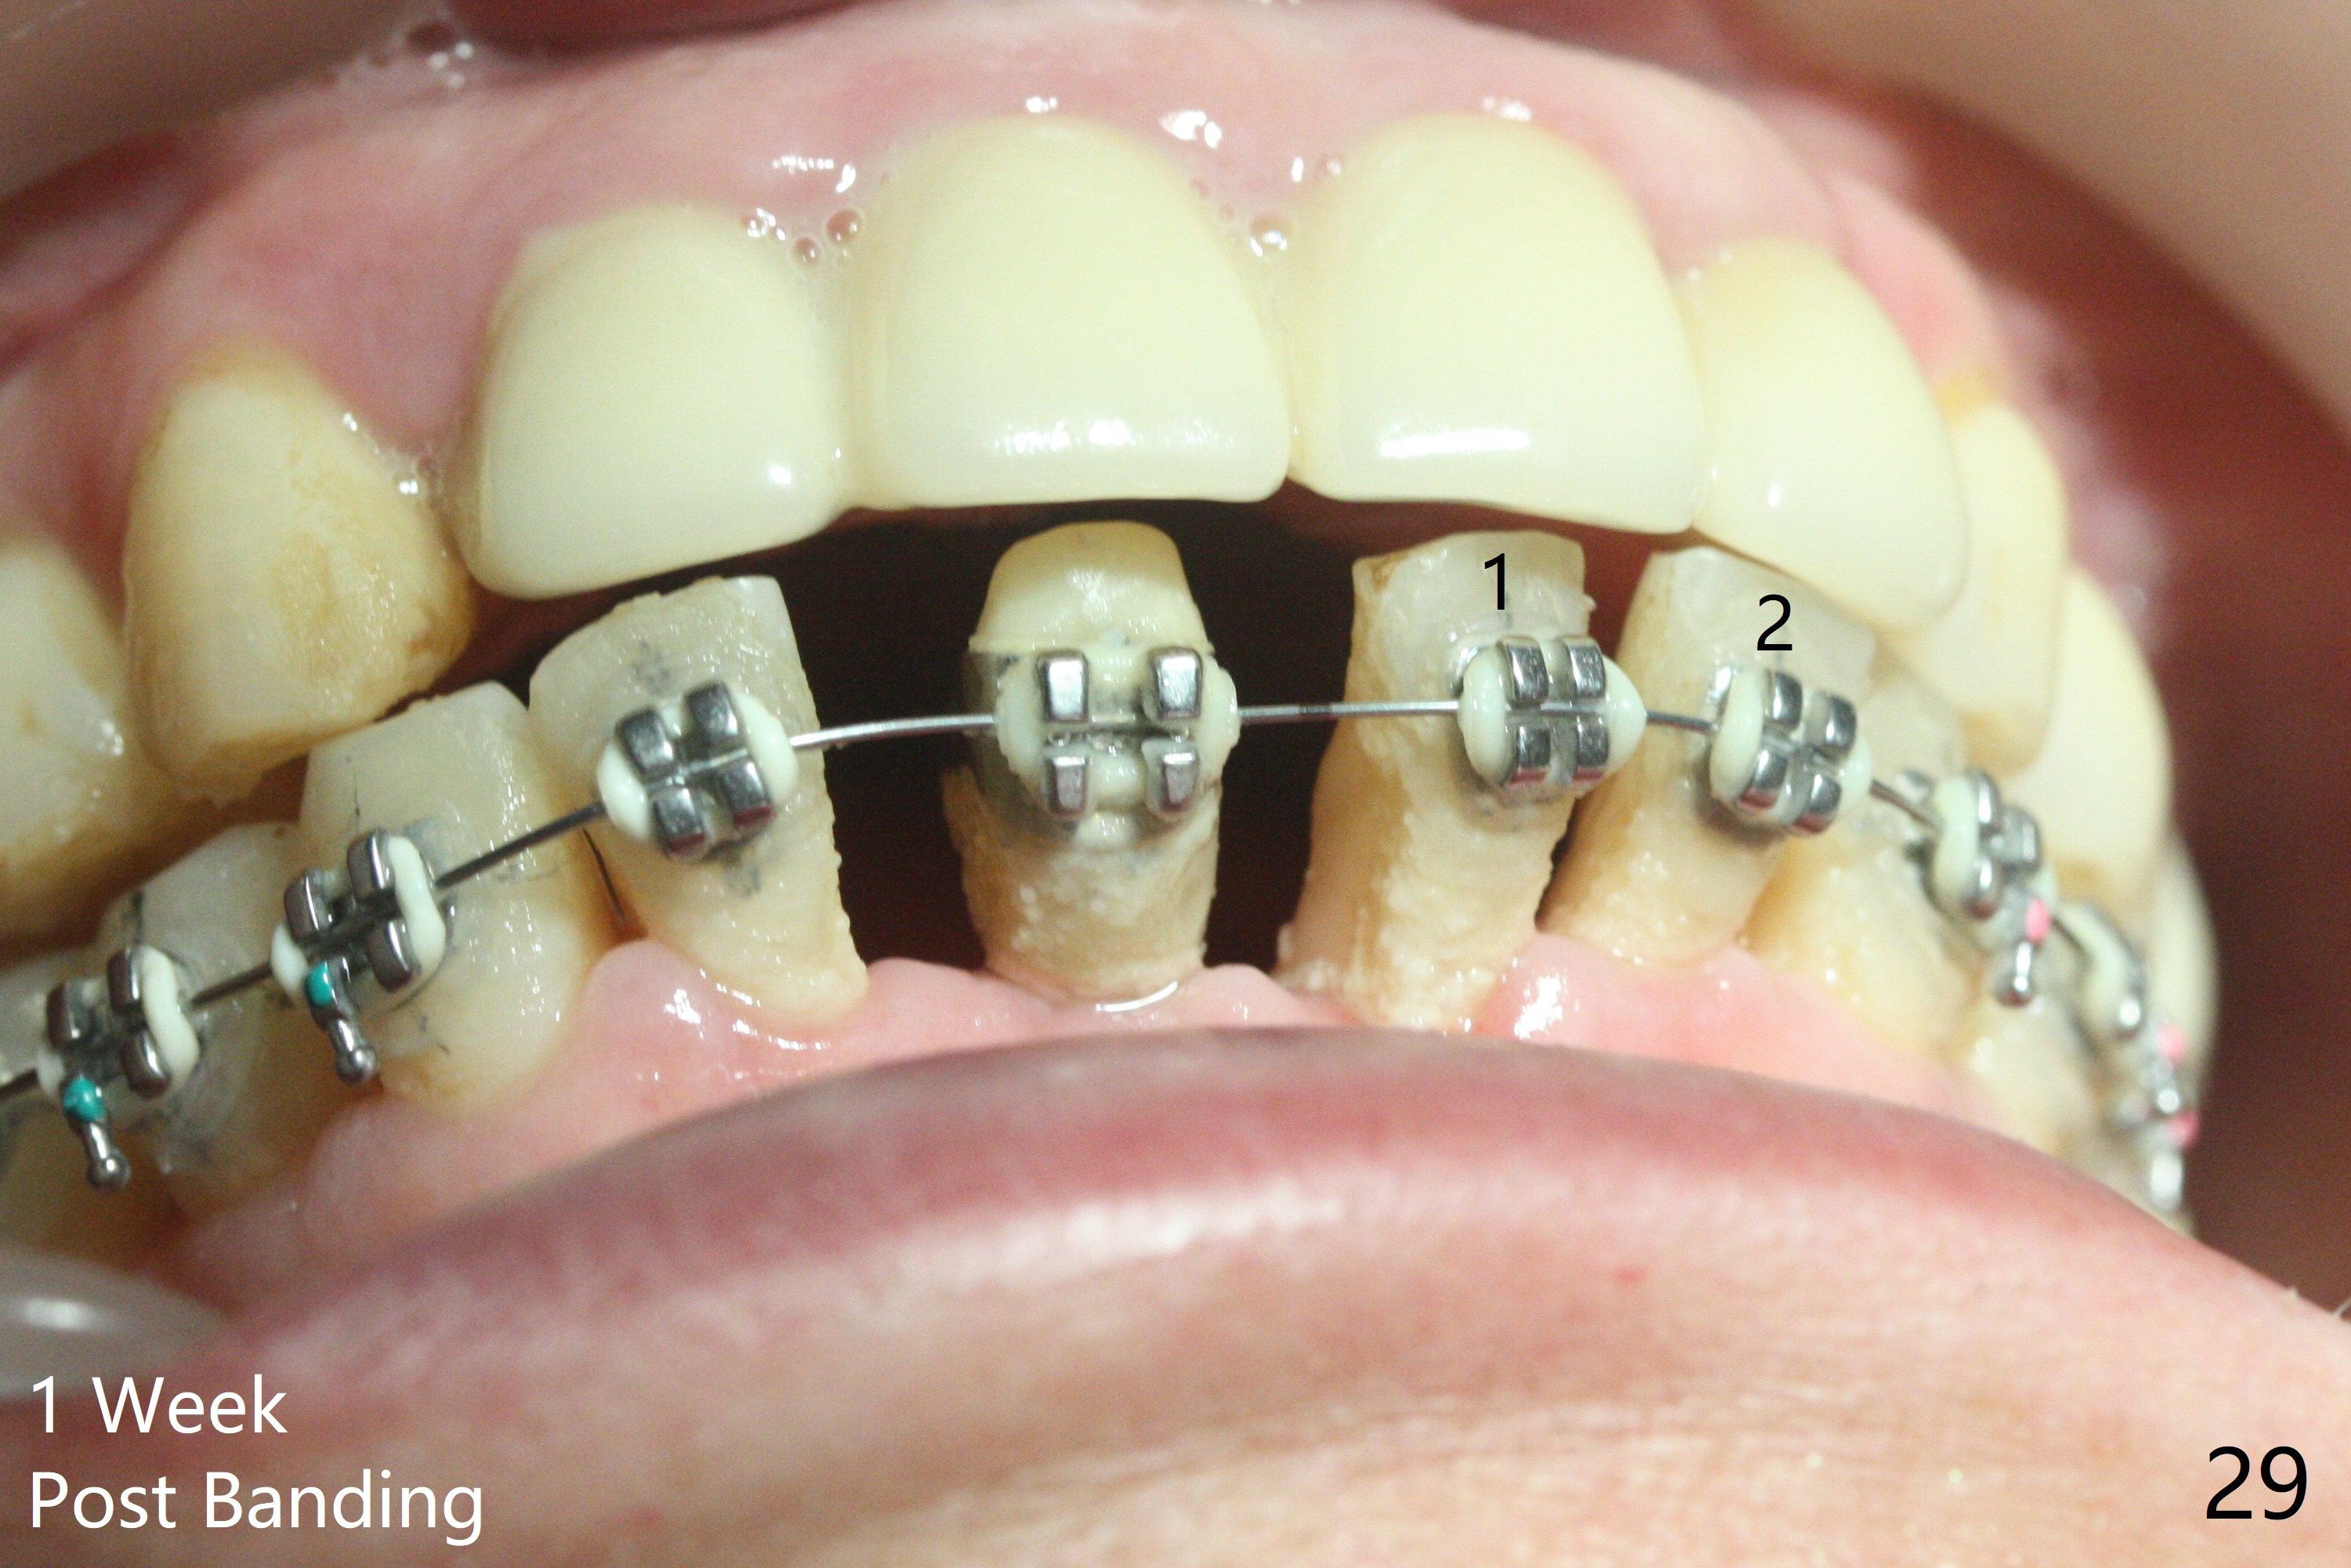

56岁女十分恐惧治疗,缺失右下1,其余切牙由于骨质吸收颊侧移位(图一:1,2),但是她不愿意拔除,同意右下1种植,牙周骨手术,植骨;植体整合后作为支抗,矫正移位下门牙。为了防止忘记舌侧瓣分离,先做舌侧切口(图二),然后颊侧瓣松弛分离(图三),包括使用前牙隧道刀(图四)切断颊侧骨膜,松弛到颊侧瓣能向舌侧牵拉3-4毫米(图五),舌侧瓣骨膜下广泛,深部分离(好像不能切断骨膜,图六),放置导板,磨平狭窄的牙槽嵴(图七:O(osteotomy)),植入2.5x12(4)毫米一段式植体(图八:故意舌侧植入,以便以后矫正),在颊侧骨板打多个出血洞(图八:箭头),然后把在平的器皿上形成的粘性骨板(sticky bone,图九),放置于植体和移位切牙周围(图十),接着使用消毒过的橡皮障punch(图十一(纸头相当于PRF膜;事先给助手示范))在三个PRF膜(图十二)打洞,套在植体和门牙上(图十三: 箭头),防止膜(图十四)和骨块(图十五,十六:*)移位,最后还必须使用最原始方法牙周敷料保护伤口(图十七)。术后9天,舌侧牙周敷料脱落,伤口稍微裂开(图十八)。术后18天撤除敷料,伤口裂开处有新鲜肉芽组织生长(图十九(*:下面是填入的骨粉,将是增宽的牙槽嵴(如果你是乐观主义者)),二十)。病人十分感激我们帮助她度过难关。她的确有sleep apnea,否定tongue thrust。术后三个月植体周围没有明显骨质吸收(图二十一至二十三),左下1,2轻度反合(图二十四),植体周围软组织健康(图二十五),5-5安置矫正器(图二十六,二十七,12 niti)。一周后下切牙向舌侧移动(图二十八),左下1,2反合纠正(图二十九)。再一周变化不大(图三十),植牙圈有些松动,两周后将重做临时牙冠,槽往舌侧移动。结果病人提前回来,植牙槽舌侧移位。一周后右下2不适(图三十一),尝试近中牵引(图三十二)。